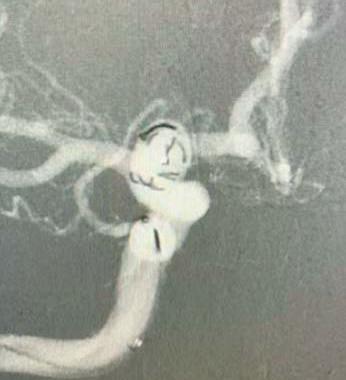

In light of a recent publication detailing the safe and effective use of the Solitaire X 3mm (Medtronic) stent retriever in medium- and distal-vessel occlusion (MeVO/DVO) stroke, Marios Psychogios (University Hospital Basel, Basel, Switzerland) discusses the relevance of having a dedicated device for these cases, as well as providing insight on what he feels is the “next frontier” in mechanical thrombectomy.

“We were one of the first clinics that used the device in Europe, and we are happy with it,” Psychogios says, highlighting navigability and radial force as being among key characteristics of the Solitaire X 3mm. “Generally, I like these aspects—the navigability for those superiortrunk M2 and M3 occlusions is really good, and it still has enough radial force to actually be able to capture clots [in those locations].”

Writing in the Journal of Clinical Medicine, Psychogios et al recently published findings from a retrospective study involving 68 consecutive primary and secondary MeVO/DVO stroke cases treated via thrombectomy across 12 European centres.1 Psychogios is keen to emphasise “really good” reperfusion results reported in the paper—as per the study’s primary endpoint, the Solitaire X 3mm achieved a first-pass rate of complete or nearcomplete reperfusion (modified treatment in cerebral infarction [mTICI] 2c–3) of 32.3%.

Other key statistics he highlights are a final-pass mTICI 2c–3 rate of 67.6%, a final mTICI 2b–3 rate close to 90%, and—regarding safety endpoints—a 13% rate of intracranial haemorrhage (ICH), with none of these complications being symptomatic or resulting in subsequent neurological deterioration. The researchers also observed no device malfunctions in the study. Psychogios acknowledges that retrospective analyses such as this do inevitably carry limitations and some inherent biases, but that the findings outlined here compare favourably to prior data on other stent-retriever devices.

One salient piece of advice Psychogios offers to his neurointerventional peers is to make use of these smaller, specialised stent retrievers like the Solitaire X 3mm when treating ischaemic strokes caused by MeVO/DVOs, if they have access to them at their centres. He advises against the deployment of regular (4–6mm) stent retrievers in said cases, stressing the importance of “dedicated” thrombectomy devices for tackling distal locations where more tortuous vessels are found and a greater risk of bleeding complications—most notably, clinically relevant ICHs—exists.

Psychogios says that, thanks to this newer generation of more specialised devices, his centre has the ability to treat distal occlusions more effectively, but also go after secondary distal occlusions more safely, as they can switch from using a larger stent retriever for an initial large vessel occlusion (LVO) to a smaller device like the Solitaire X 3mm within the same case if necessary.

having a dedicated device for those secondary distal occlusions leads to better safety and then probably better outcomes for the patient,” he states. “This is something that we always do and, if you have the means, I would recommend it—don’t just stay with your LVO setup! It’s good to have a ‘standard’—and we always have that—but, if you [encounter] a new condition in the angio suite, you have to adapt.”

“Another important thing is that most of the cases [78%] were done with a combined approach, with a dedicated aspiration catheter, and this is something we have been promoting and using in our patients,” Psychogios also says of the study. “With the Quattro technique, we are seeing fewer complications [at our centre], so we promote this combined approach.2 In my opinion, it is not just about the device—you need the whole setup and, usually, we combine [the stent retriever] with an aspiration catheter—but it’s also crucial that the device is correctly chosen and, for those more curved segments, the Solitaire X 3mm is a very good device.”

occlusion type. According to Psychogios, while it has been suggested that aspiration alone may be sufficient for more distal occlusions, his own experiences as well as meta-analysis data from some 2,500 thrombectomy cases point towards a higher rate of clinically relevant bleeding, and the fact “you probably don’t open the vessels as [effectively] as with a combined approach”.

Distal “truth” moves closer Psychogios also provides a brief update on the progress of the global DISTAL trial evaluating thrombectomy in primary MeVO/DVO stroke, for which he is the principal investigator: as of early February 2024, the study has enrolled 370 patients out of a targeted 530, with Psychogios anticipating finalised recruitment later in the year and, “hopefully”, initial data presentations at the start of 2025. He goes on to disclose that DISTAL very recently received approval from its data and safety monitoring board (DSMB) to continue, following a planned interim analysis that revealed no safety- or futility-related concerns.

“We will have data from randomised trials showing what is best for these occlusions next year,” he continues. “We also plan to join forces with the other trials—ESCAPE MEVO, DISTALS, DISCOUNT—to pool data. What we have at the moment is just a glimpse of the truth, and I think next year we are going to have a better overview of the whole truth. I strongly believe that, in a few years’ time, we’re going to go after those distal occlusions. We’ve seen this with the LVOs, then ‘late-window’ LVOs, and now the largecore patients, and I think this is going to be the next frontier.”